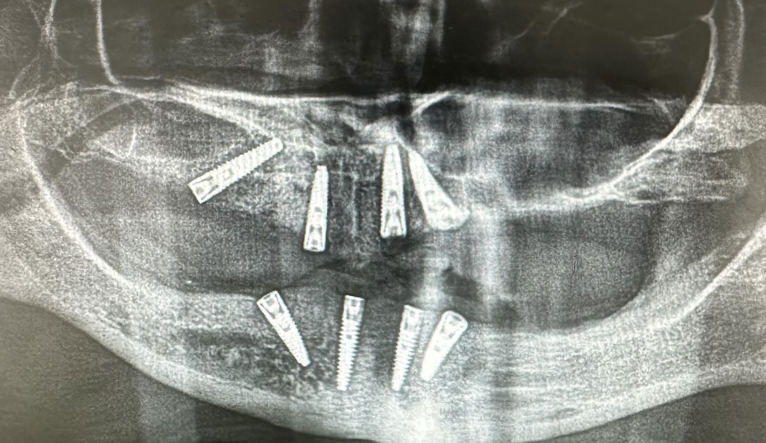

Dentalni implantati ugrađuju se u čeljust i njihovo učvršćivanje traje 3 do 4 mjeseca – kontrolira se rendgen slikom.

Kontrola rendgen slikom. Foto: Dental Centar Jelić

Postupak se izvodi u lokalnoj anesteziji i potpuno je bezbolan. Ukoliko je potrebo ugraditi više implantata, ugrađuju se istovremeno u jednoj posjeti. Nakon 3 do 4 mjeseca vrši se kontrola učvršćivanja i pristupa se izradi keramičkog mosta ili krunice.